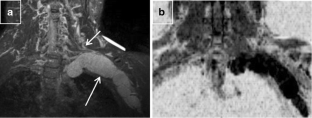

Baumer P, Kele H, Kretschmer T, Koenig R, Pedro M, Bendszus M et al (2014) Thoracic outlet syndrome in 3T MR neurography-fibrous bands causing discernible lesions of the lower brachial plexus. Eur Radiol 24:756–761